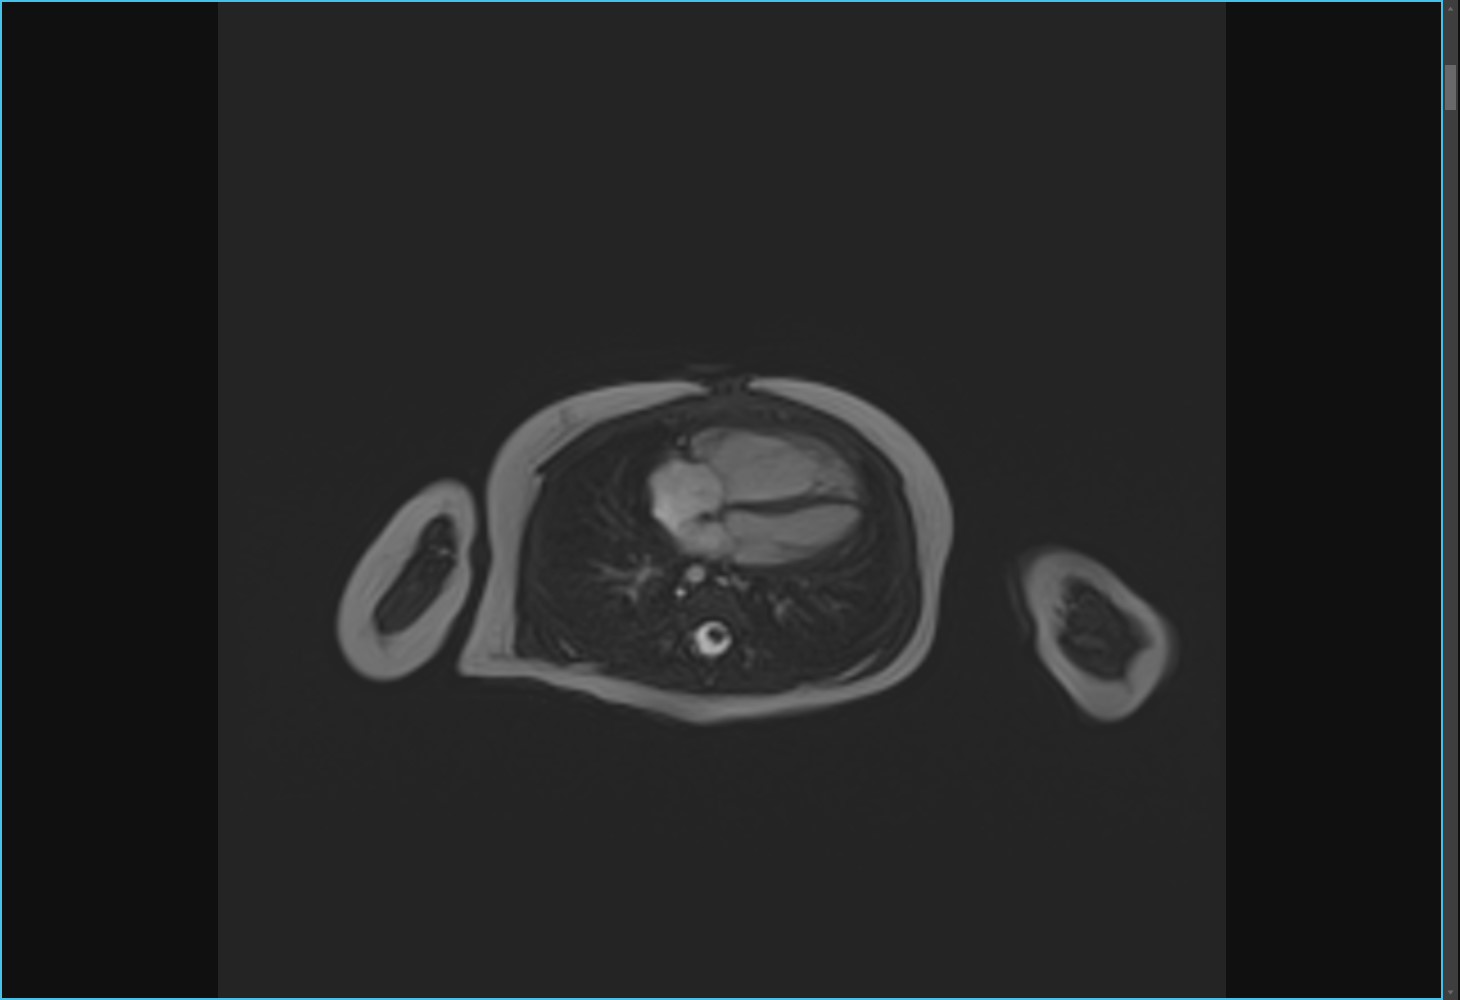

閉塞性肥大型心筋症の心臓に経皮的中隔心筋焼灼術 (PTSMA)を施した画像ですが、MRIでは造影剤を用いる事なく心臓の動きを捉えることができるだけでなく、エタノールにより壊死させた中隔心筋を明瞭に描画することができるので治療効果の判定に有用です。

PTSMA前

PTSMA後